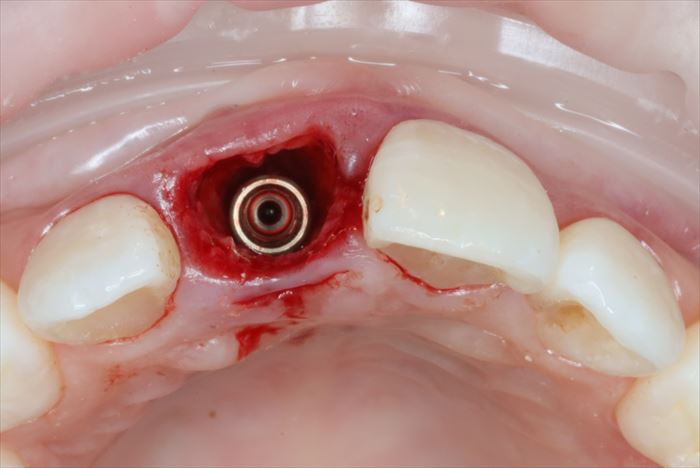

インプラント埋入用の挿入ジグを外しました。

インプラントフィクスチャー(インプラント本体)の接続部分を保護し、

歯肉の形態を形成するためのヒーリングキャップ(高さ6㎜)を準備します。

_

ヒーリングキャップを締結しました。

歯根の方がインプラントよりも太いため隙間が生じます。

わずかな隙間は血液が貯留して骨となることが判っていますが、念のため骨移植材を準備します。